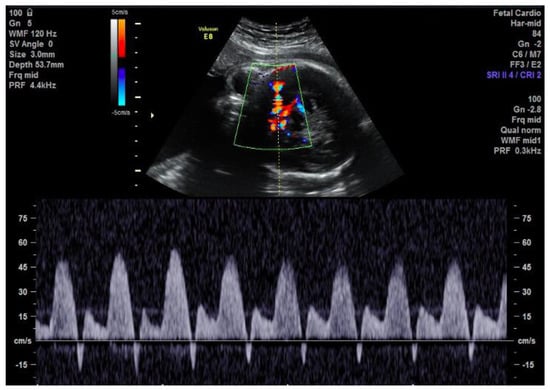

Figure 2.

Brief early diastolic reversal of flow in the MCA seen on the spectral Doppler due to the reversal of flow in the ascending aorta.